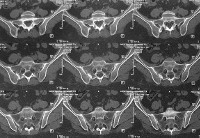

MRI of the sacroiliac joints.

МРТ крестцово-подвздошных суставов. Неинвазивный метод диагностики, позволяющий визуализировать крестцово-подвздошные суставы путем сканирования радиоволнами в условиях сильного магнитного излучения. Он предоставляет серию изображений с последующей программной обработкой и созданием объемной модели исследуемых анатомических структур. Это наиболее информативный способ визуализации хряща, связок и мышц этой области. Он используется в качестве дополнительного метода исследования при недостаточной информативности рентгеновских и компьютерных томографов при диагностике воспалительных, дегенеративных, травматических и онкологических поражений. Он имеет высокую диагностическую ценность при раннем выявлении сакроилеита у пациентов с болезнью Бехтерева, а также при распознавании некоторых видов серонегативного артрита.